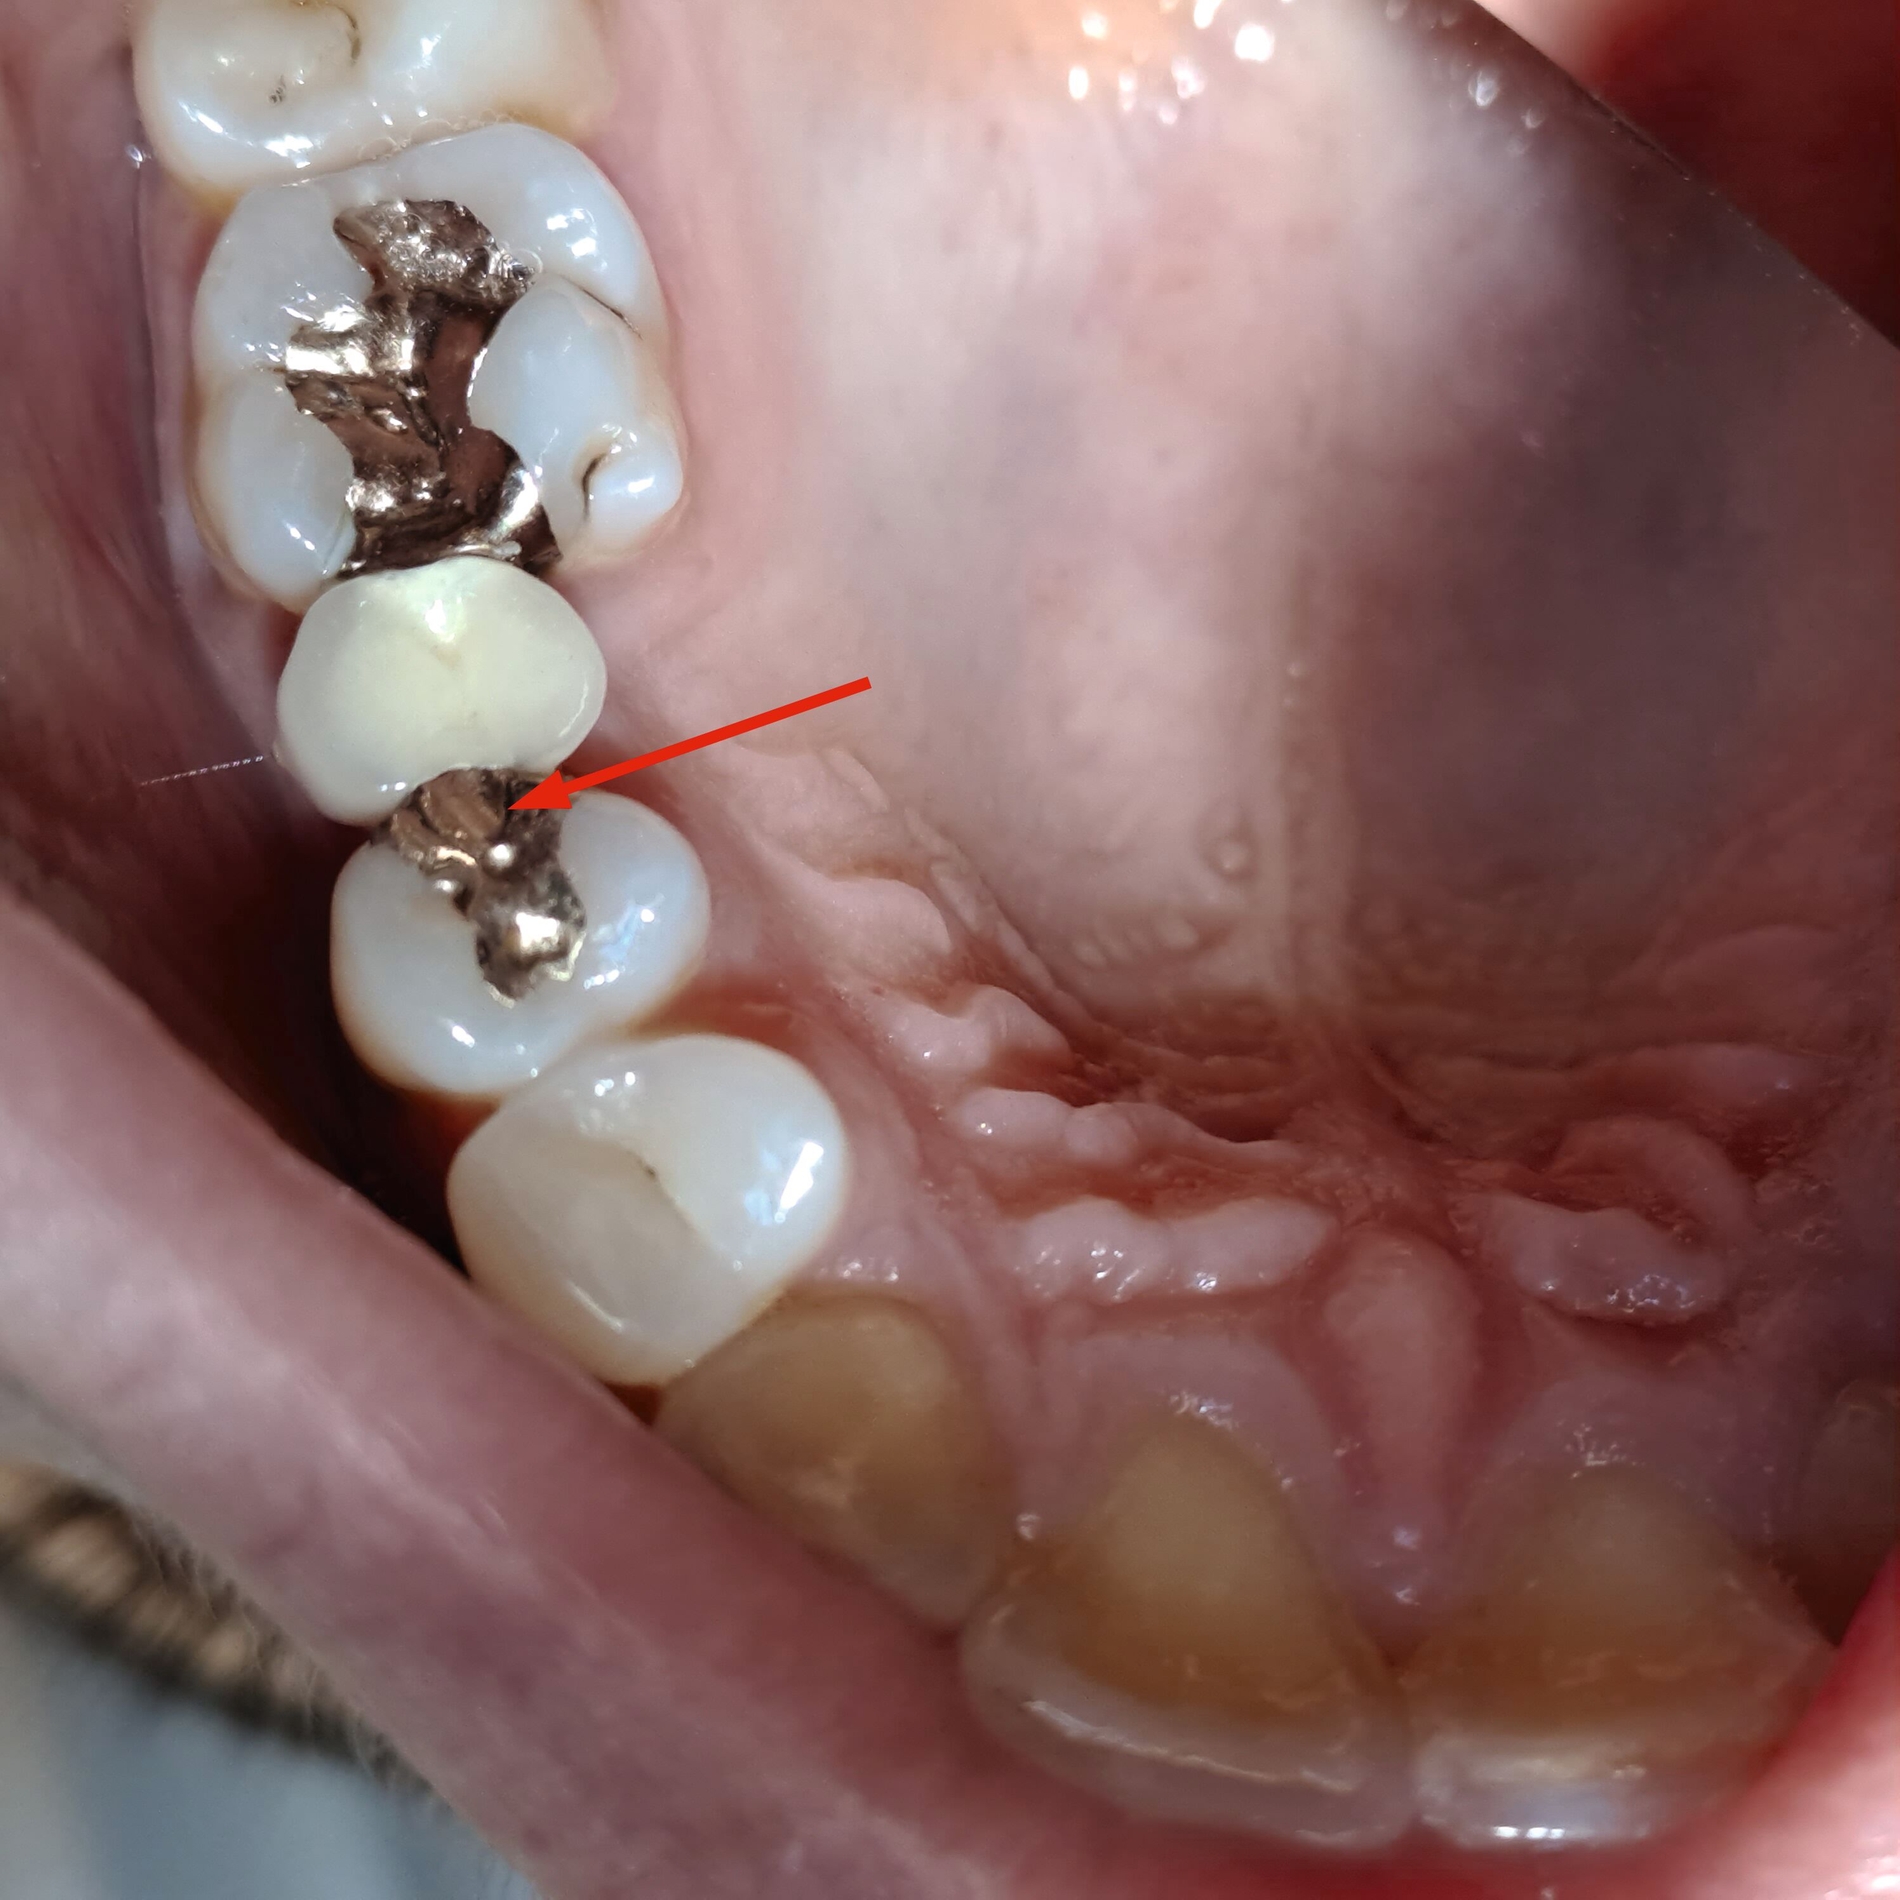

Die fertige Minibrücke besteht aus:

dem zementierten Anker (Krone oder Inlay), gegebenenfalls verblendet,

dem Brückenglied, in der Regel verblendet, und

der freien, metallischen Auflage auf dem Zahn jenseits der Lücke.

Die Minibrücke dient manchmal vorwiegend der horizontalen Abstützung. Kronen als Anker können distal oder mesial der Lücke sein; meine Anker-Inlays lagen bisher alle distal. Ich empfehle die Beschränkung auf Prämolaren-große Lücken, wenn der Anker ein Inlay ist.

In den Abbildungen werden drei Fallbeispiele vorgestellt, bei denen alle Brücken noch in situ sind: